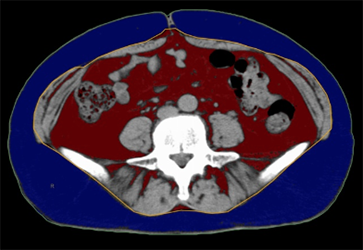

内臓脂肪測定 【2,200円】

X線CTを用いておへそのあたりの内臓脂肪面積を測定します。内臓脂肪過剰の場合は高血圧、糖尿病、高脂血症、動脈硬化などは、生活習慣病の誘引になるといわれています。

赤が内臓脂肪 青が皮下脂肪